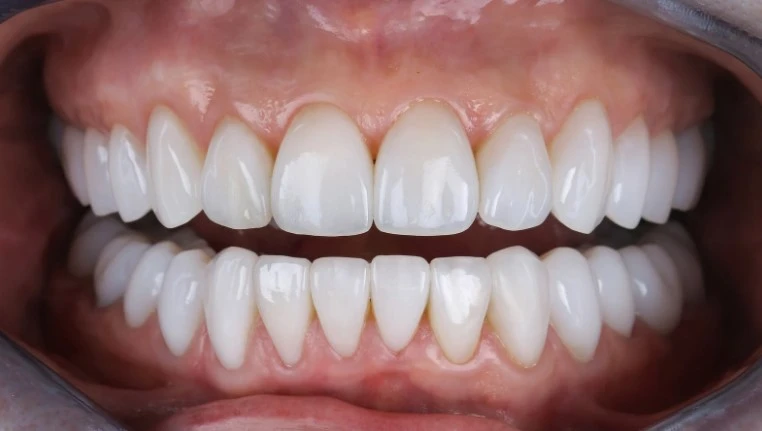

Далее следуют этапы снятия слепков и цифрового планирования будущей конструкции, что позволяет заранее спрогнозировать результат и согласовать все нюансы с пациентом. После изготовления постоянного протеза проводится его примерка и фиксация. Современные материалы и технологии, применяемые в стоматологических клиниках Алматы, обеспечивают не только долговечность, но и максимальную естественность внешнего вида зубов.

Компания Benefakta Dental обращает особое внимание на помощь пациентам в адаптации после протезирования поддерживая не только медицинский, но и психологический комфорт. Тщательный подбор цвета и формы коронок позволяет полностью имитировать натуральную улыбку, что особенно важно для молодых людей и специалистов, ведущих активную социальную жизнь.